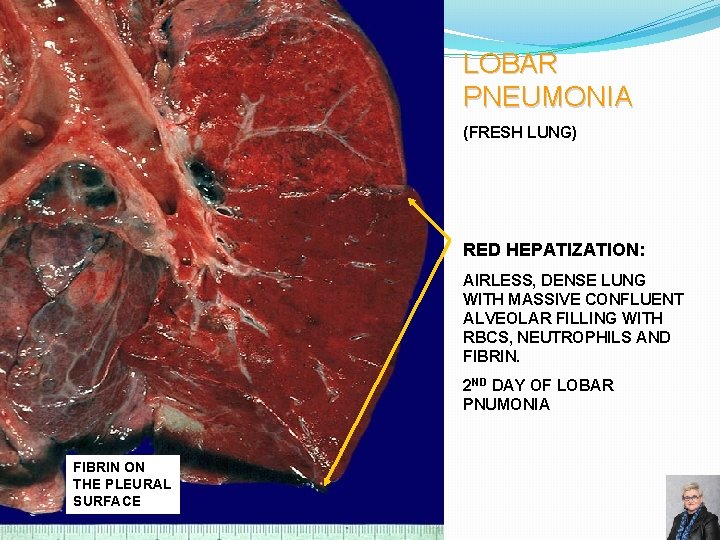

LOBAR PNEUMONIA (FRESH LUNG) RED HEPATIZATION: AIRLESS, DENSE LUNG WITH MASSIVE CONFLUENT ALVEOLAR FILLING WITH RBCS, NEUTROPHILS AND FIBRIN. 2 ND DAY OF LOBAR PNUMONIA FIBRIN ON THE PLEURAL SURFACE 60